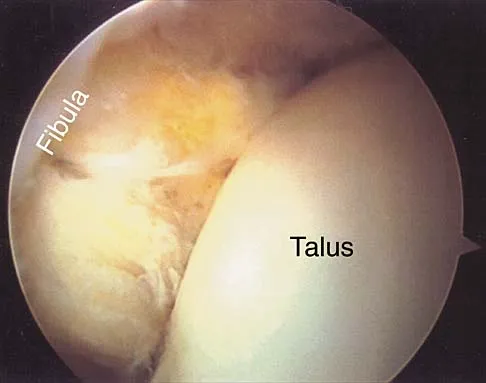

Question 48:

An 18-year-old hockey player sustains an acute anterior shoulder dislocation that requires manual reduction. At arthroscopy, the lesion shown in Figure 24 will be observed in what percent of patients?

Correct Answer: 80% to 95%

Explanation:

The clinical photograph shows an acute capsulolabral avulsion from the anterior glenoid, also referred to as a Perthes-Bankart lesion. In patients who sustain an acute dislocation that requires a manual reduction, this pathologic lesion is observed with high frequency. In several research studies, it has been visualized in 80% to 95% of patients at arthroscopy. Taylor DC, Arciero RA: Pathologic changes associated with shoulder dislocations: Arthroscopic and physical examination findings in first-time, traumatic anterior dislocations. Am J Sports Med 1997;25:306-311.